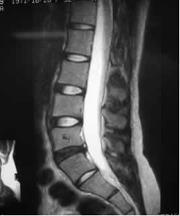

Does Your MRI Look Like This?

MRI Image of Low Back Lumbar Spine with Disc Compression

Notice the darker color of the injured and compressed spinal disc. This is a common finding of an injured herniated disc and a degenerative disc.